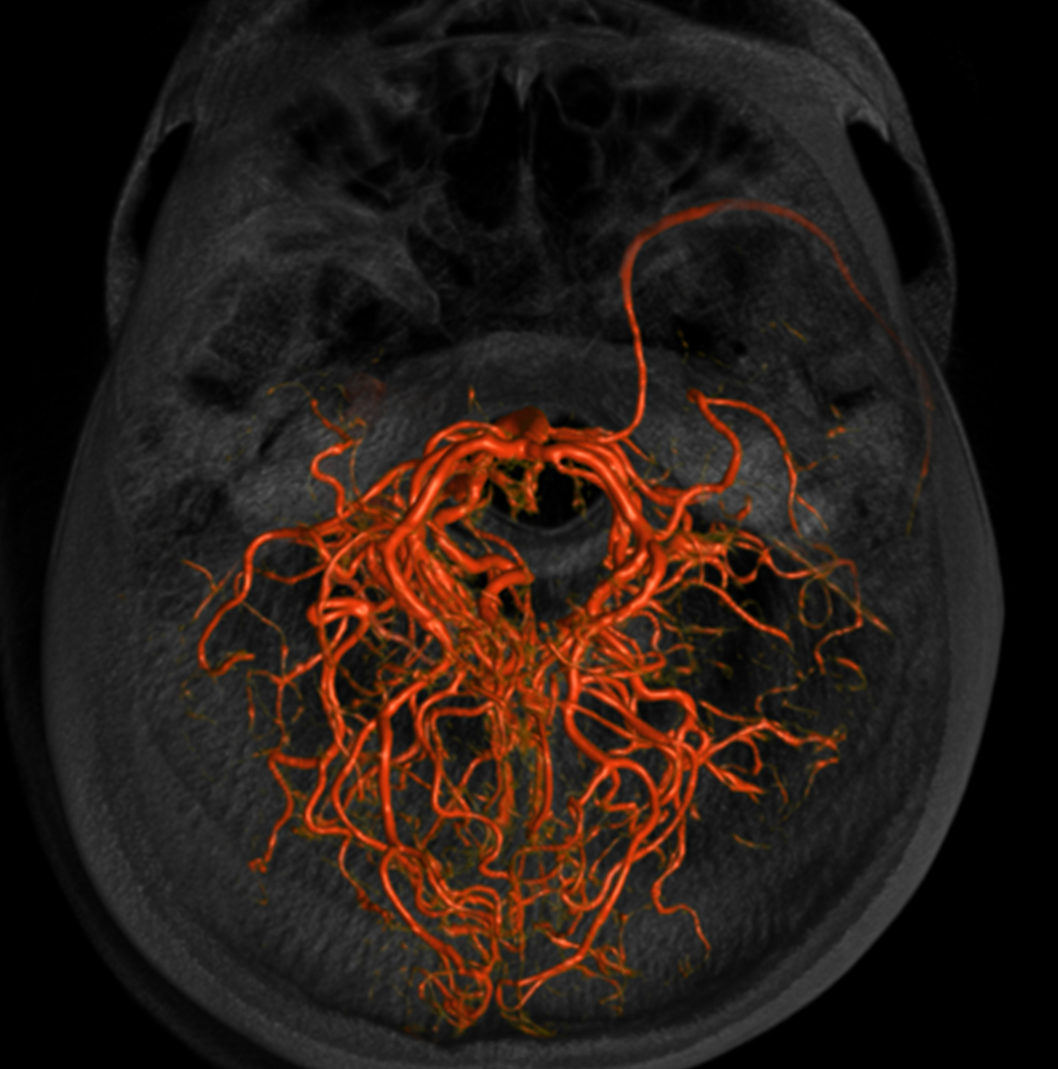

And, in case you really dont believe its the trigeminal artery, check out these co-registration images of angio (axial MIP reconstructions of rotational angio) and finally with superimposed tractography of the Vth nerve! Images courtesy Dr. Nader Delavari

Superimposed MRI and angio axials (our trigeminal artery is shown bi arrow)

Now with tractography of CN V